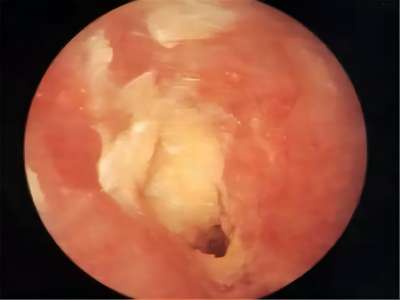

外耳道炎外耳道结黄痂图

外耳道炎在检查时显示有很多黄色分泌物,附着在外耳道黏膜壁上,脓痂上还有白色豆腐渣状的鳞屑堆积,患者自觉耳痛、瘙痒、耳道潮湿。